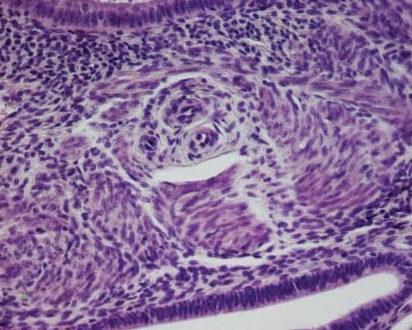

Лейомиоматозная пролиферация обнаруживалась также в цитогенной строме очагов Ам, в непосредственной топографической связи с сосудами микроциркуляторного русла (рис. 2). В ряде случаев на основе гладкомышечных пролифератов вокруг очагов Ам формировались множественные микрои макроскопически видимые лейомиомы (рис. 3).

Рис. 2. Лейомиоматозная пролиферация в цитогенной строме ЭГ в непосредственной топографической связи с сосудами микроциркуляторного русла. Окраска – гематоксилин-эозин, ув. х400